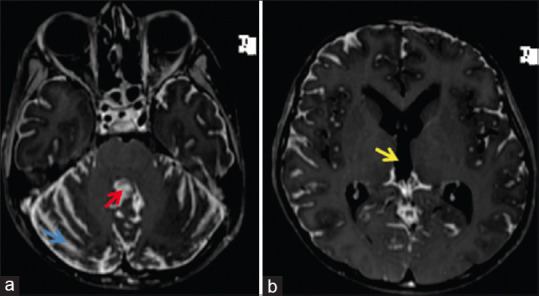

原发性弥漫性脑膜原始神经外胚层肿瘤是一种罕见的脑膜肿瘤,可伪装成慢性脑膜炎。虽然临床表现和放射学特征可为这种疾病提供线索,但脑膜活检是确诊的关键。在这种情况下,对经验性治疗无效的神经感染病例进行重新评估时,必须保持高度的怀疑和较低的门槛。我们介绍了一个 9 岁男孩的病例,他因慢性脑膜炎伴脑积水开始接受抗结核治疗。脑膜活检显示他患有原发性弥漫性脑膜原始神经外胚层肿瘤。

Primary diffuse leptomeningeal primitive neuroectodermal tumor is a rare meningeal neoplasm which can masquerade as chronic meningitis. While the clinical presentation and radiological features may provide a clue to this condition, meningeal biopsy is essential to clinch the diagnosis. A high index of suspicion and a low threshold for re-evaluating cases of neuroinfection that do not respond to empirical therapy are essential in this scenario. We present the case of a nine year old boy who was initiated on antituberculous treatment for chronic meningitis with hydrocephalus. Meningeal biopsy revealed a primary diffuse leptomeningeal primitive neuroectodermal tumor.